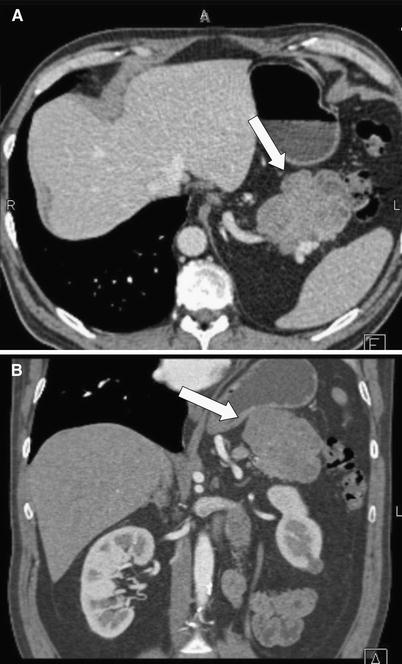

Fig. 1 A 71-year-old male with acinar cell carcinoma of the pancreatic uncinate process. Axial (A) and coronal volume rendered (B) images demonstrate a homogeneous, hypodense mass exophytically extending inferiorly from the uncinate process.